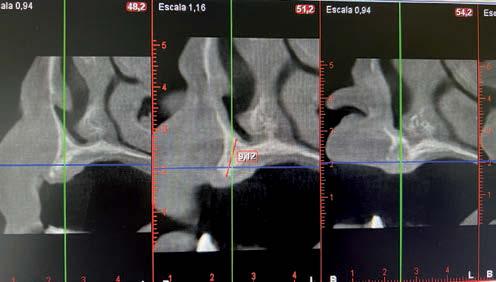

técnicas de abordaje de seno maxilar: elevación convencional o la inserción de implantes cortos y extra-cortos mediante elevación transcrestal, desde enero de 2010 en adelante. Todos los pacientes fueron estudiados antes de la inserción de los implantes mediante modelos diagnósticos, exploración intraoral y realización de un TAC dental (Conebeam) analizado posteriormente mediante un software específico (BTI-Scan II).